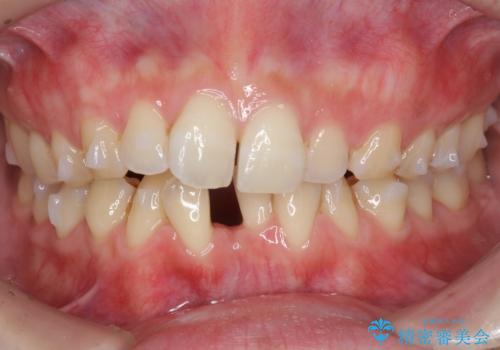

前歯のガタつき インビザラインで 下の前歯を1本抜歯

- 前歯のがたつきを主訴に来院。マウスピース矯正を希望されました。

治療にあたり、下の前歯を一本抜歯しています。

非抜歯で無理に治療をしようとすると、下の前歯の骨が薄く歯ぐきが下がったり、歯がぐらついたり、がたつきが完全にとれないリスクがあることを説明しました。

下の前歯が3本になるため、上下の正中は合わない仕上がりとなりますが、正中を合わせるには上下左右4本抜歯の上、ワイヤー矯正となってしまいます。

それよりは抜歯の数も少なく、メリットが大きいのではないかと説明し、選んでいただきました。

短期間できれいな歯並びになり、大変満足していただきました。